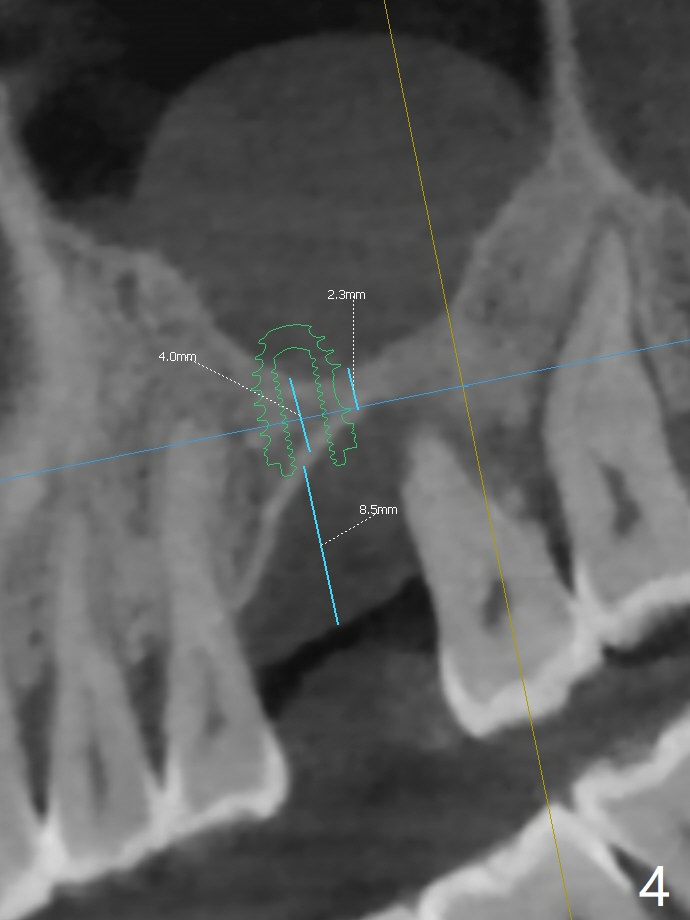

47岁男(吸烟一天半包)因右下8疼痛就诊,口服抗生素疼痛消失,不愿意拔除,但是要求左上6植牙(图一),左上颌窦好像有粘液囊肿(图一,三:*),而右侧上颌窦粘膜更厚(图二)。左上6植牙床是一个斜面,植牙会远中偏移,导板设计应有意往近中(图三:红线)。植体远中根尖需要内提升,冠部需要植骨(图四),厚的粘骨膜有利于植骨(粘骨,使用mill abutment),骨粉尽可能放置7牙根近中(图五:红色圆圈,Endogain)。第二种设计(图六)使用细长植体,近中龈下4毫米,远中龈下8毫米,有利于植骨,覆盖远中暴露的螺纹。Return to No Caries 位点保存/导板 手术 提升 Xin Wei, DDS, PhD, MS 1st edition 10/28/2020, last revision 04/04/2021